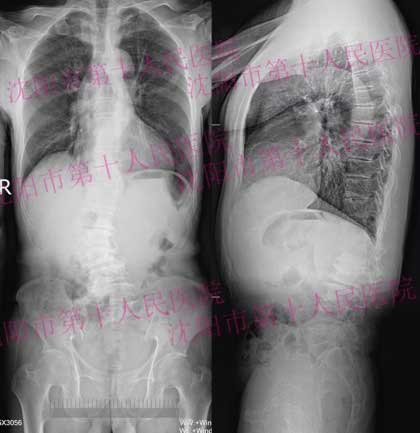

典型病例1:男性患者,64岁,腰痛伴右下肢麻木、无力多年,只能走几十米的路,严重影响生活质量。

DR显示:腰椎段明显向右侧弯,椎体不同程度旋转,椎间隙变窄,腰1-3间盘区及腰4-5间盘积气。

常规治疗方式需要超长节段椎弓根钉内固定,后路多阶段松解、减压。使脊柱后柱结构及稳定性严重破坏,同时也刺激硬膜造成神经损伤等并发症。存在对患者损伤大,经济负担重,恢复慢,并发症多,需二次手术取出内固定等问题。

通过OLIF入路,巧妙的、微创的解决问题。术后患者右下肢麻木、无力症状彻底解除,同时也纠正了脊柱侧弯、旋转畸形,恢复了脊柱正常高度与序列,很快可下地正常行走。通过术后随访,患者自诉:“不仅腰板挺直了,还长个了,现在不再需要家人照顾,还可以做力所能及的家务,对疗效十分满意”。